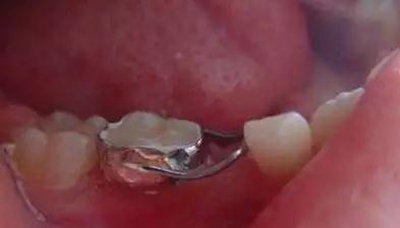

③帶環(huán)絲圈式間隙保持器。

制作:在基牙上做帶環(huán)或全冠,再在其上焊接絲圈,絲圈的頰舌徑比后繼恒牙的頰舌徑稍寬。絲圈與牙尖接觸位置要在其遠(yuǎn)中最突點或稍下方。與第一恒磨牙接觸點應(yīng)在近中外形高點。